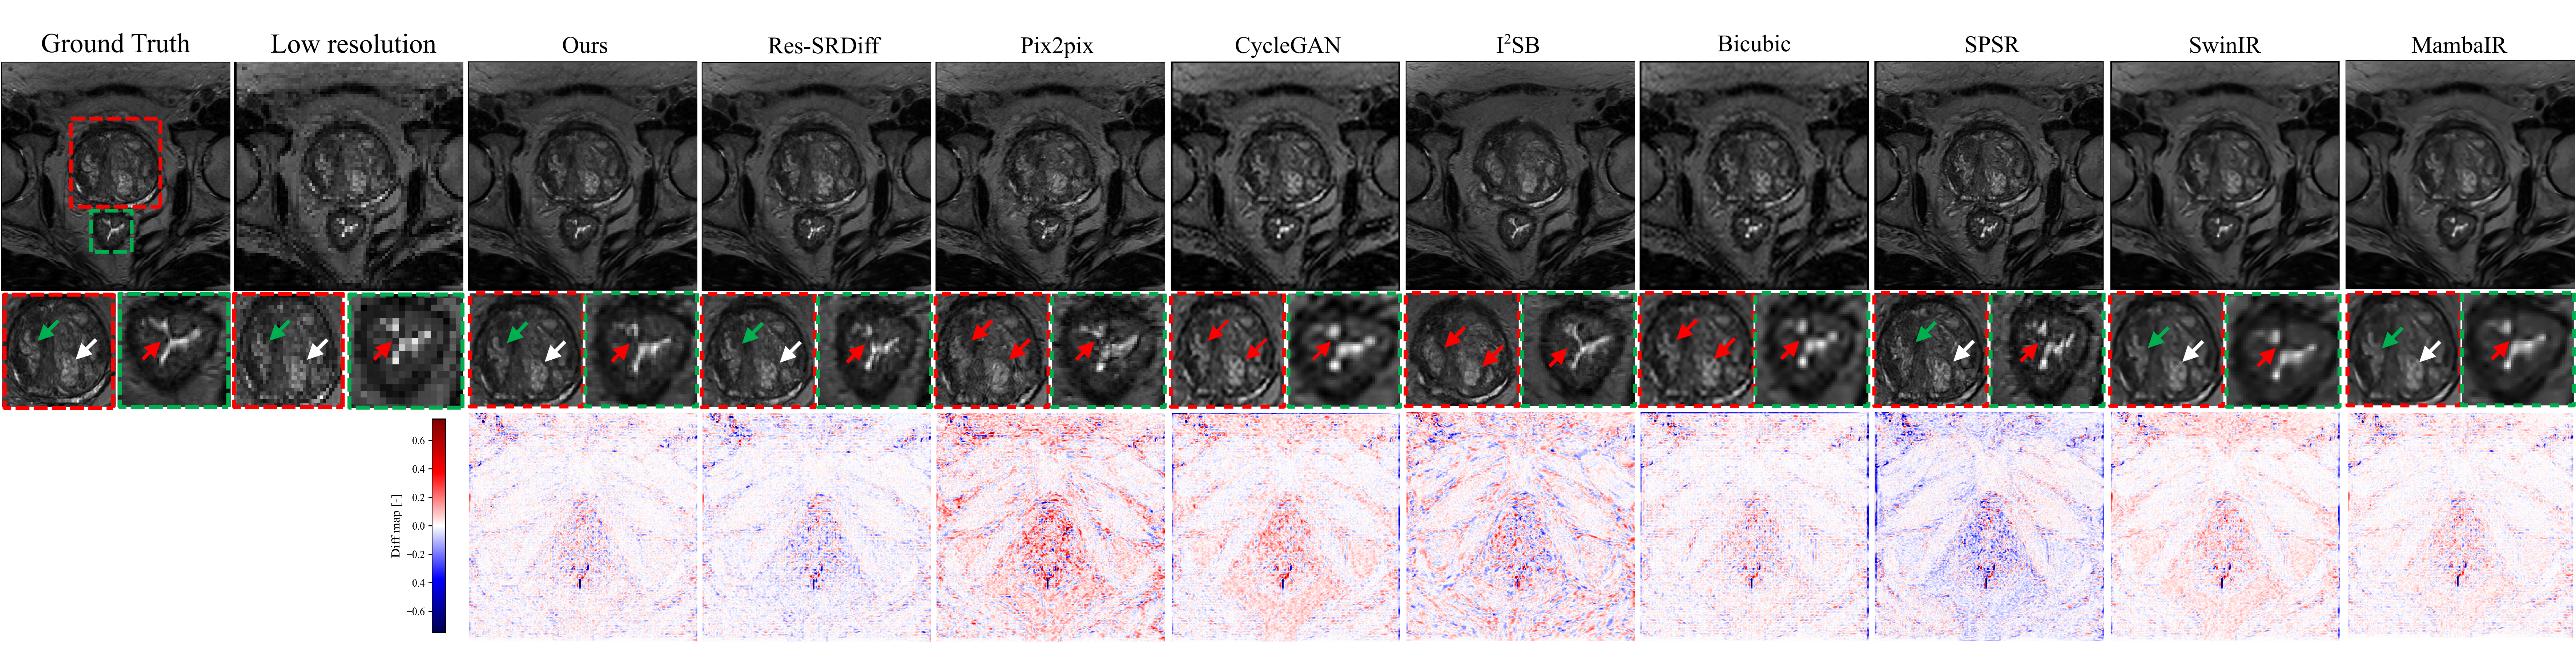

Figure 5 presents a qualitative comparison of super-resolution results on axial T2w pelvic MRI. The ground-truth HR image (leftmost) clearly delineates anatomical boundaries, including the prostate capsule (green arrow), lesion region (white arrow), and surrounding structures (red arrow). Bicubic interpolation fails to recover fine anatomical detail, producing blurred boundaries and oversmoothed textures. GAN-based approaches such as CycleGAN and Pix2pix partially restore high-frequency components but introduce hallucinated structures and amplified noise, as seen in irregular residual patterns. SPSR demonstrates improved texture recovery, although boundary sharpness remains suboptimal. Transformer-based SwinIR shows reasonable global consistency but exhibits edge oversmoothing in fine tissue boundaries, while Mamba-based MambaIR captures local details but occasionally introduces minor artifacts in homogeneous regions. Diffusion-based methods (I2SB and Res-SRDiff) achieve higher fidelity, yet residual artifacts and structural inconsistencies are still visible in lesion-adjacent regions.

Figure 5: Visual comparison of super-resolution approaches on a representative axial prostate T2w MRI slice. Top panels display the ground truth image together with outputs from competing reconstruction methods. The second row provides magnified views from prostate and bladder regions of interest, chosen to emphasize structural detail. Colored arrows indicate specific aspects under evaluation: green arrows indicate edge delineation of fine tissue, white arrows indicate continuity of anatomical features, and red arrows indicate areas sensitive to artifacts. The bottom panels show voxel-wise difference maps relative to the ground truth.

In contrast, the proposed method reconstructs sharper anatomical edges and preserves tissue continuity, closely matching the ground-truth HR reference. Lesion boundaries and the prostate capsule are more accurately delineated, and residual maps confirm lower reconstruction error relative to competing approaches. These qualitative findings align with the quantitative results summarized in Table 1, demonstrating that our model not only enhances perceptual similarity but also reduces distortion and preserves diagnostically relevant structures.